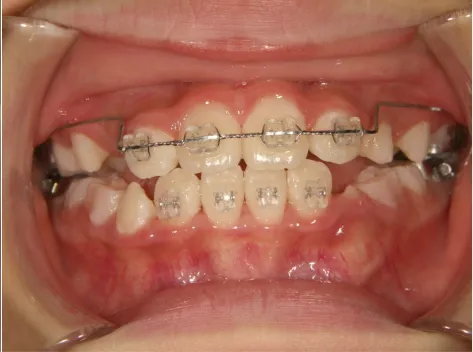

治療中⑧高1:15y11m 抜歯治療中

治療中⑨高2:17y1m 抜歯治療中